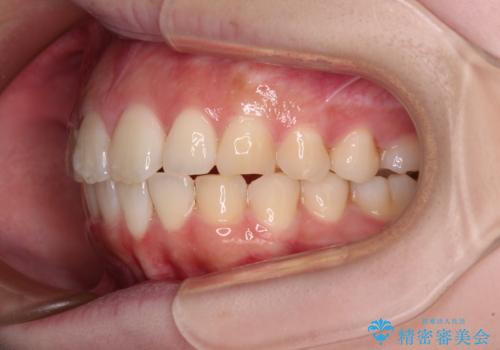

前歯のデコボコをインビザラインできれいに整える

- 前歯のデコボコと上下の隙間を気にして来院された患者様です。

前歯の捻れを改善するとともに、口元が少しでも引っ込むように治療計画を立て、仕上げることができました。